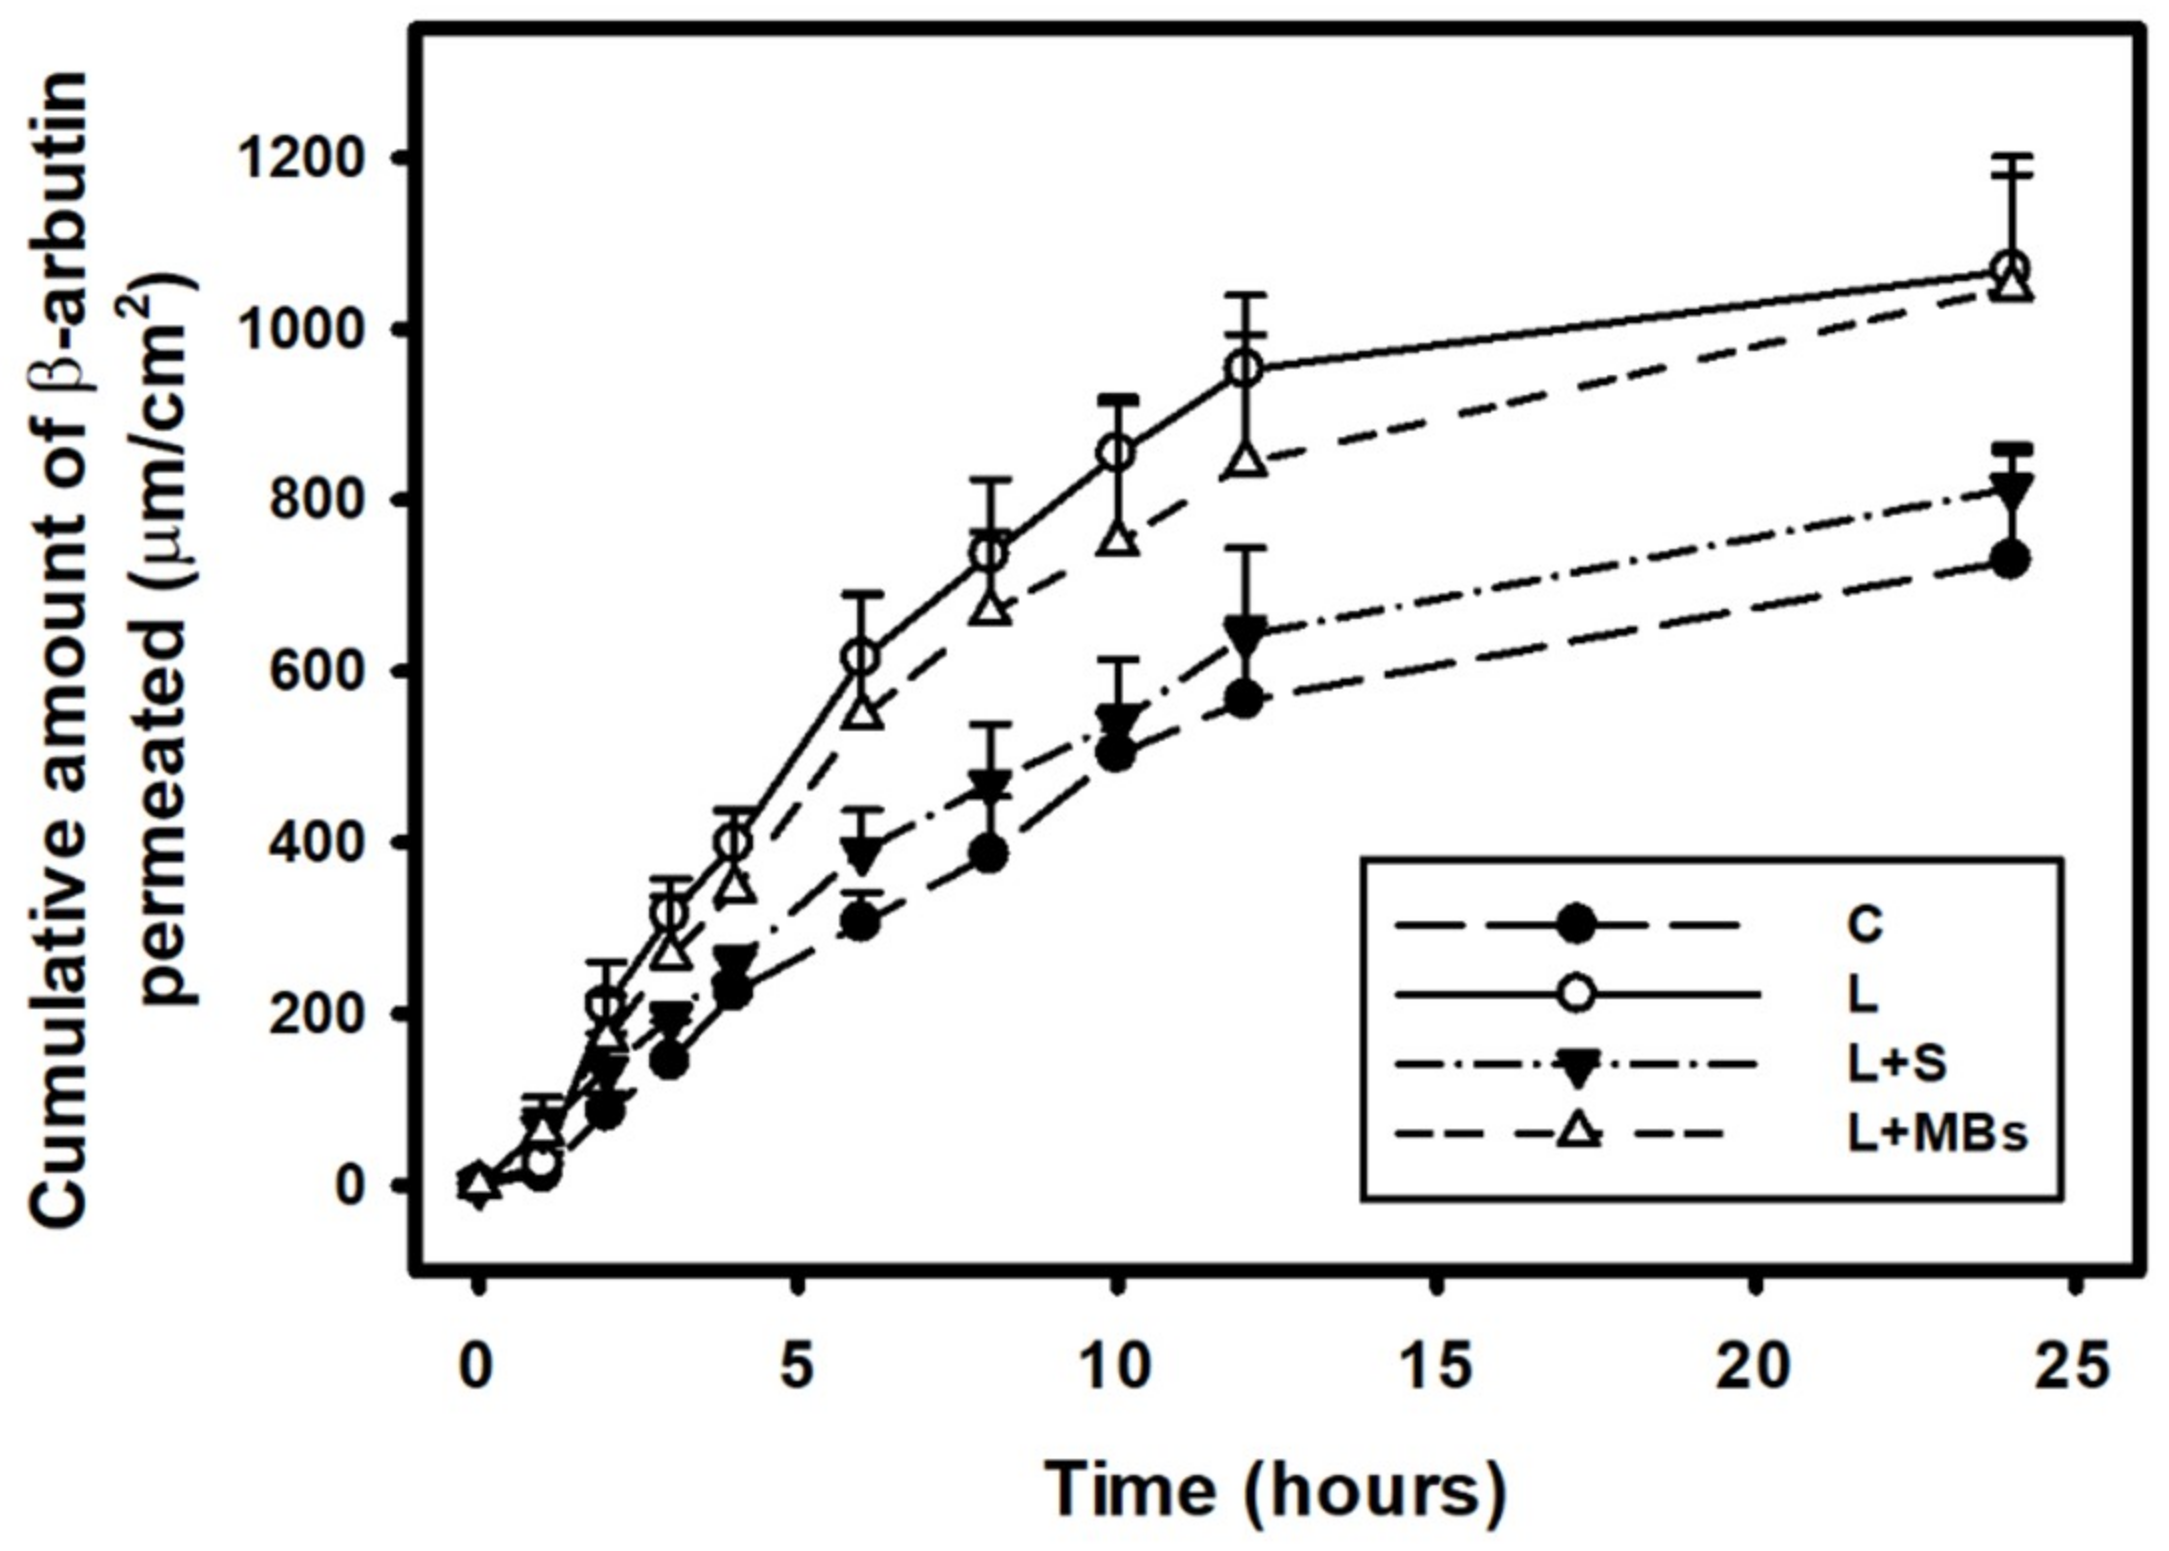

3.3. In Vitro Skin Penetration by the β-arbutin Solution